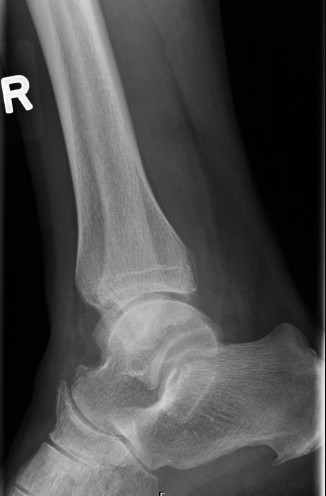

Q

error

A

external rotation